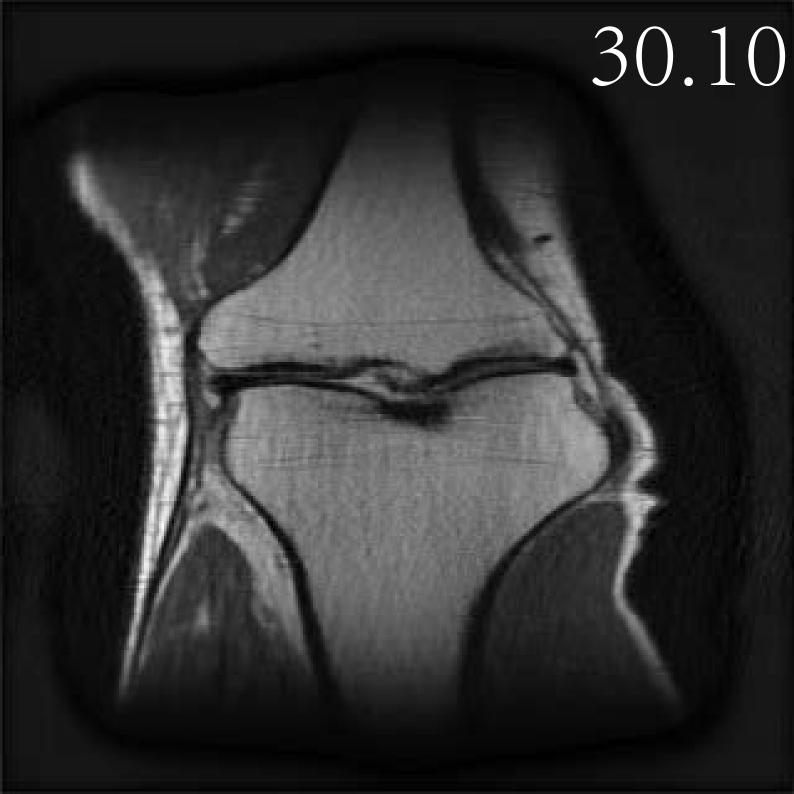

4.2.3 Accelerated Multi-coil MRI

In this subsection, we report the comparative performance of EI, SkEI and C-SkEI in multicoil MRI reconstruction task. We evaluate the performance of two distinct Sketched-EI methods proposed in this study for multicoil MRI, using a knee MRI image with 15 coils from zbontar2018fastmri . Subsequently, we performed a comparative analysis of the reconstruction results under two distinct sketch schemes and varying sketch sizes. Consistent with Section 4.2.1, we begin by comparing our proposed methods with the vanilla DIP method, considering the same DIP network architectures as outlined in Section 4.2.1.

For SkEI and C-SkEI schemes, SS is defined as the sketch operation that samples N15N\leq 15 coils from the original 15 coils, then forms a minibatch named ASNA_{S_{N}}. However, these two sketch schemes differ in their minibatch partition strategies. Specifically, as described in Algorithm 3, Coil-Sketch compresses the initial 15 coils and then selects the first LL compressed virtual coils as the new multi-coils. Subsequently, the first RR higher-energy virtual coils are retained, while the last SS lower-energy virtual coils undergo sketch operation. In contrast, Classical-Sketch directly acts on the original 15 coils, randomly sampling the NN coils into a minibatch. During each iteration, the minibatch is randomly chosen from the 15 coils for updates. For this study, we experiment with N=10,5N=10,5 and 22, respectively.

The visualized comparisons are shown in Figure 9, as can be seen, the performance of the DIP method is still suboptimal, consistent with findings from the sparse view CT experiments. In comparison, the EI method achieves remarkable improvements in reconstruction quality due to the EI regularizer. Furthermore, the reconstruction results generated by these two proposed sketch methods exhibit almost no loss in performance and even surpass the vanilla EI method. Furthermore, as presented in Figure 11 (b), the time cost per iteration of the sketched EI decreased compared to the vanilla EI method. Specifically, C-SkEI-2coils decreased 19% per iteration compared to vanilla EI, while SkEI-2coils (with subsampling sketches) decreased 17%. Moreover, we observe that C-SkEI demonstrates a much faster convergence rate compared to that of standard EI.

Refer to caption

AyA^{\dagger}y

DIP

*EI-full (15coils)

SkEI-5coils

C-SkEI-5coils

xx (GT)

Figure 9: Multi-coil MRI Images (with corresponding PSNR) reconstructed by DIP, EI and our two Sketched EI methods, where ‘SkEI-’ shorts for classical-sketch and ‘C-SkEI’ for coil-sketch. ‘*’ denotes the baseline.